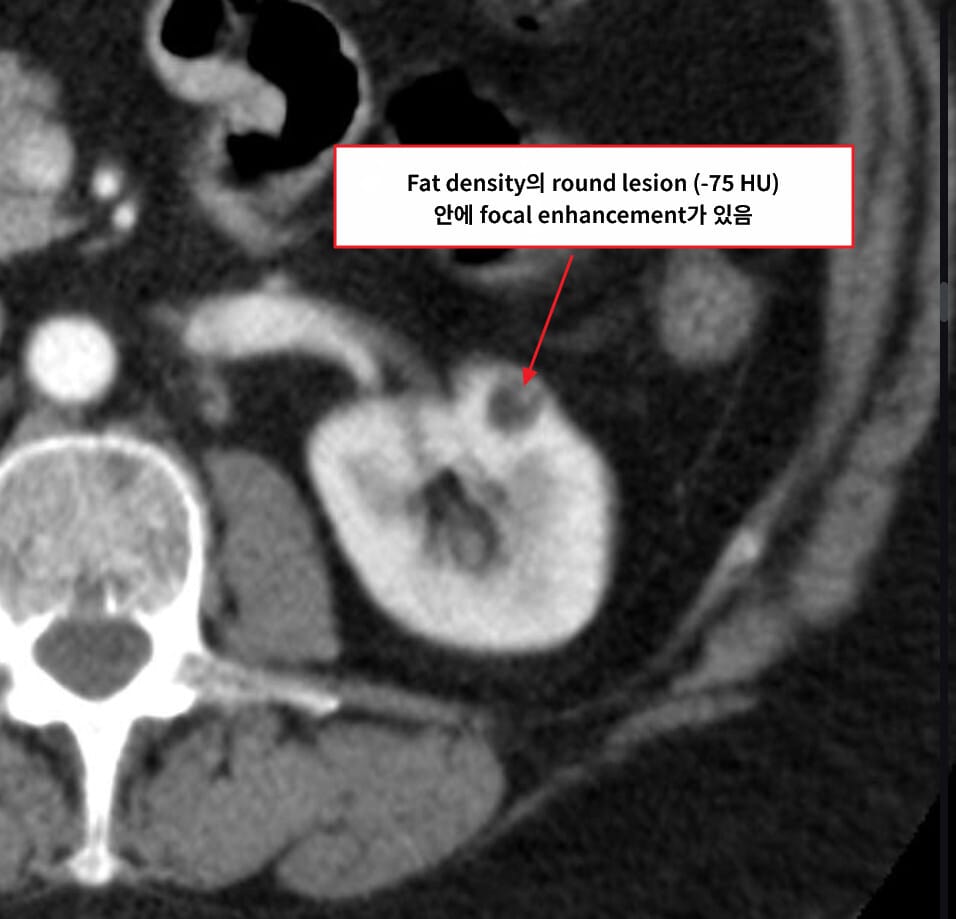

[진단]

– CT/MRI에서 지방 성분(−HU) 확인

Schubert R, Renal angiomyolipoma. Case study, Radiopaedia.org (Accessed on 19 May 2025) https://doi.org/10.53347/rID-16842